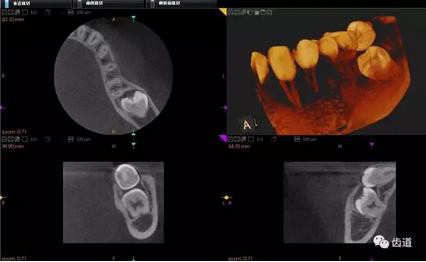

下頜第二第三磨牙阻生CBCT影像定位

三種圖片的影像學(xué)比較

CBCT在牙種植修復(fù)中的應(yīng)用。種植前利用CBCT對(duì)患者的牙床進(jìn)行檢查,可精準(zhǔn)判斷牙槽骨的寬度、厚度及高度、骨的密度、重要的顏面神經(jīng)、血管和鼻竇位置等。臨床醫(yī)生不僅可以在計(jì)算機(jī)直觀的看到牙槽骨的立體影像,還可以切換不同的視角來(lái)觀察硬組織之間的位置關(guān)系,在手術(shù)方案中避開(kāi)危險(xiǎn)區(qū)域,保證手術(shù)的安全性。臨床醫(yī)生還可以利用CT數(shù)據(jù)進(jìn)行數(shù)字模型重建,配合軟件預(yù)先做好手術(shù)模板,使種植手術(shù)更安全快捷,避免在種植手術(shù)過(guò)程中不慎破壞神經(jīng)、鼻竇等解剖結(jié)構(gòu),導(dǎo)致顏面神經(jīng)麻痹、鼻竇炎等并發(fā)癥的發(fā)生。

1、下頜骨種植牙前測(cè)量準(zhǔn)備影像